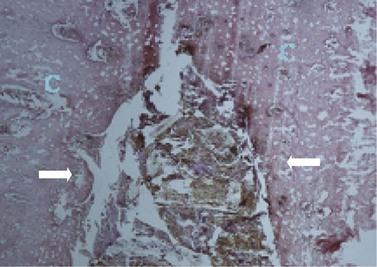

In brachydont teeth, periodontal disease starts with loss of the normal tight gingival attachment between adjacent teeth. This gingiva then becomes inflamed due to mechanical irritation, e.g., to impacted food particles and from chemical irritation from bacteria, food, and plaque. As the gingival destruction continues, the gingival defect becomes further impacted with food, and the process perpetuates itself with the periodontitis extending deeper into the periodontal ligament and also to the buccal and lingual margins of teeth, forming large periodontal food pockets16 (Figs 10.1310.15). This inflammation and infection may even extend to the alveolar bone, and even supporting bones, causing alveolar bone remodeling and even bone necrosis and infection. Eventually the tooth becomes loose and may even spontaneously be shed due to loss of supporting structures.40 More localized extension of the periodontal disease can lead to infection of the pulp, apical infection, and ultimately death of the tooth.42,46 A periodontal disease grading system (0–4) used in small animals that is based on the percentage of dental attachment loss42 could be used in equids (Table 10.1).

image

Fig. 10.13 Decalcified histological image of the base of a valve CT diastema showing erosion and hyperplasia of the gingiva in the interproximal space. (Original magnification ×100.)

(Courtesy of Alistair Cox and Sionagh Smith.)

Fig. 10.14 Decalcified histological section of subgingival connective tissue in the interproximal space of a CT diastema showing moderate infiltration with mononuclear inflammatory cells. (Original magnification ×200.)

Fig. 10.15 Localized periodontitis where a neutrophilic infiltration (n: inset lower right) is present within the gingiva (g), and the peripheral cementum (pc) has already receded through carious attack (H and E).